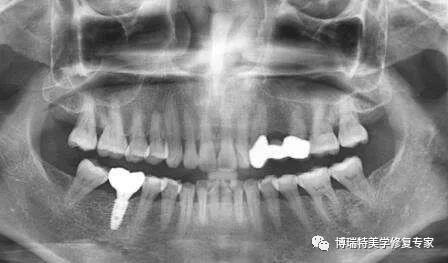

自体牙移植

自体牙移植是临床上可以选择的一种治疗缺失牙的手段,将健康无功能的牙或者正畸需要拔除的牙完整拔出后,再植于缺失或者不能保留患牙的部位,从而恢复正常咬合功能的一种治疗方法。移植牙的来源主要包括正畸减数牙、埋伏牙、阻生牙、多生牙等。然而,由于其严格的适应证和术后常见的并发症,如炎性吸收、骨质粘连等,使牙移植术在临床上的应用受到了一定的限制。

近年来,随着对自体牙移植预后因素研究的不断深入,以及多学科综合治疗的发展,牙移植术后成功率和存活率均有了显著的提高。目前,已有大量研究对牙移植与正畸治疗的结合应用进行了尝试,结果表明正畸治疗不仅能为自体牙移植提供良好的应用条件,同时通过加载合适的正畸力,还可以提高牙移植的疗效。